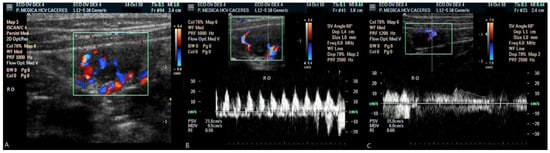

| RO | PSV | 20.79 | 1.44 | 19.50 | 1.54 | 11.97 | 1.6 | 12.50 | 1.53 |

| EDV | 8.09 | 0.78 | 8.20 | 1.05 | 5.15 | 0.88 | 5.65 | 0.76 | |

| RI | 0.61 | 0.03 | 0.59 | 0.03 | 0.58 | 0.02 | 0.55 | 0.02 | |

| LO | PSV | 20.30 | 3.14 | 19.92 | 1.99 | 10.94 | 1.26 | 13.03 | 1.41 |

| EDV | 6.72 | 0.8 | 7.40 | 0.08 | 4.20 | 0.52 | 5.82 | 0.98 | |

| RI | 0.66 | 0.02 | 0.63 | 0.02 | 0.62 | 0.01 | 0.58 | 0.03 | |